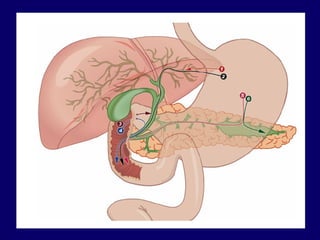

Tipos de técnicas ecoguiadas: Drenaje biliar por  Rendezvous Hepatogastrostomia Giovannini et al, 2003 Coledocoduodenostomia  Giovannini et al, 2001 Coledocoantrostomia  Artifon et al, 2010 Drenaje en derivaciones gastrointestinales Estenosis benigna  Estenosis maligna DRENAJE BILIAR ECOGUIADO

Hepatogastrostomia Giovannini et al., 2003 Acceso a los  ductos hepáticos del lóbulo izquierdo cercanos a la ventana  ecoendoscópica de la pared gástrica proximal Acceso trans-hepático Prótesis plástica / metálica DRENAJE BILIAR ECOGUIADO

Coledocoduodenostomia ecoguiada: 2001 – Giovannini et al. Varios casos descritos (Ang et al., 2007; Tarantino et al., 2008; Kahaleh et al, 2008; Irisawa et al, 2009; Perez-Miranda., 2009; Itoi et al., 2008; Artifon et al., 2010) Acceso extra-hepático DRENAJE BILIAR ECOGUIADO

Coledocoantrostomia ecoguiada:  Drenaje de vía biliar principal para el estómago distal (antro), con utilización de ecoendoscopia Neoplasia biliopancreatica con infiltración del bulbo duodenal Artifon et al, GIE 2010 (in press) DRENAJE BILIAR ECOGUIADO